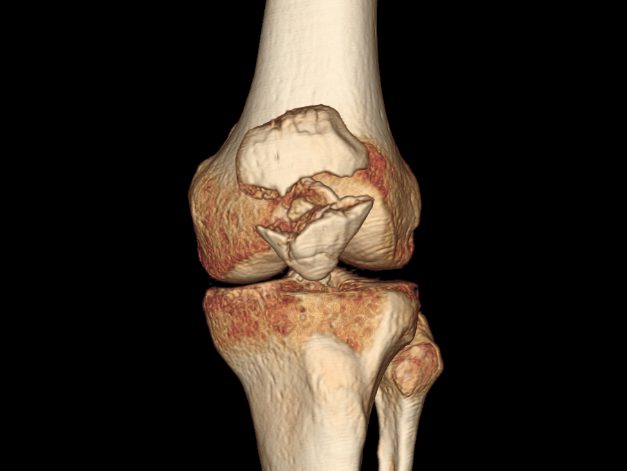

Деформирующий остеоатроз

Наиболее распространенная болезнь коленных суставов. По статистике, каждый третий человек, имеющий проблемы с коленями, страдает именно от этой патологии. Деформирующий остеоатроз обычно развивается в возрасте более 40 лет. Чаще всего страдают женщины, спортсмены, лица с избыточной массой тела и люди, выполняющие тяжелую физическую работу.

Деформирующий гонартроз – это хроническое дегенеративно-дистрофическое заболевание, ведущее к постепенному разрушению внутрисуставных хрящей. При отсутствии адекватной терапии патология ведет к прогрессирующему снижению работоспособности и даже инвалидности. Но правильное своевременное лечение не позволяет избавиться от остеоартроза, а всего лишь замедляет его развитие.

На начальных стадиях симптомы этой болезни коленного сустава слабо выражены или вовсе отсутствуют. Со временем больного начинают беспокоить ноющие боли в суставе, возникающие после резкого вставания со стула, во время ходьбы, при подъеме по лестнице. Вскоре заболевание приводит к выраженному нарушению подвижности колена.

Таблица 2. Степени развития гонартроза

| Степень | Клиническая картина | Лечение | Течение и прогноз |

| I | Периодические несильные боли, исчезающие после отдыха. Незначительная, быстропроходящая отечность. Отсутствие деформации | Коррекция образа жизни, лечебная физкультура, ношение ортопедической обуви. Обезболивающие мази, хондропротекторы в виде таблеток | Не мешает человеку вести привычный образ жизни. Вызывает некоторый дискомфорт при физических нагрузках. При адекватном лечении не прогрессирует и не приводит к осложнениям |

| II | Частые выраженные боли, характерный хруст. Появление скованности, затрудненности при движениях. Начальная деформация коленных суставов | ЛФК, физиотерапия, массаж. Применение обезболивающих, противовоспалительных средств, хондропротекторов, препаратов кальция. Фонофорез с гидрокортизоном или внутрисуставное введение кортикостероидов | Затрудняет выполнение простых действий и мешает человеку вести привычный образ жизни. Правильное консервативное лечение улучшает состояние больного, приостанавливает разрушение суставных хрящей |

| III | Постоянные сильные боли при ходьбе, резкое ухудшение подвижности колена. Заметное увеличение объема, деформация сустава | Лекарства, ЛФК, медикаментозная терапия малоэффективны. Они незначительно облегчают самочувствие человека, но не помогают полностью избавиться от неприятных симптомов | Вызывает резкое снижение трудоспособности. Чтобы избавиться от постоянных болей, снова начать нормально ходить, человеку требуется операция |